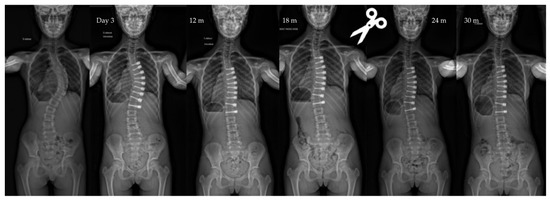

| Pre-op | Post-op Day 3 | Post-op 1y | Last f/u | p-Value | |

|---|---|---|---|---|---|

| Major curve | 49°(8,9°) | 27°(12°) | 22°(12°) | 19°(14°) | <0.01 |

| Secondary curve | 27°(14°) | 23°(15°) | 22°(11°) | 17°(10°) | <0.01 |

| Instrumented curve | NA | 26°(11°) | 23°(10°) | 20°(14°) | <0.01 |

| Kyphosis (T1–T12) | 20°(13°) | 23°(13°) | 25°(12°) | 24°(14°) | 0.06 |

| Lordosis (L1–L5) | 36°(12°) | 32°(13°) | 40°(7°) | 40°(8°) | 0.07 |

| Cranial screw slippage | 6 (7%) | Thor. | - | 18 months po |